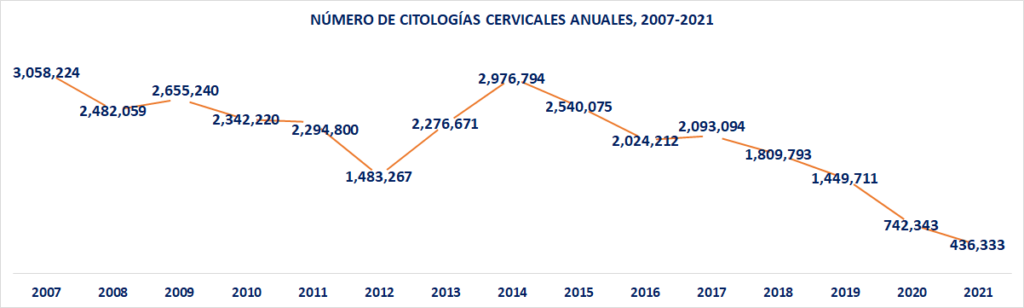

Se desploma la detección temprana

Sin embargo, como se comentó, hay una drástica caída en el número de citologías cervicales realizadas por la Secretaría de Salud. En efecto, en el 2007 se realizaron 3.058 millones de este tipo de estudios. Para el periodo de 2008-2011 el promedio anual fue de 2.44 millones; del 2012 al 2018 la cifra promedio anual se redujo otra vez a 2.17 millones de estudios.

Frente a estos datos, en el año 2019 el número de citologías cervicales se redujo a 1.44 millones, es decir, 50.6% menos que el promedio anualizado registrado en la administración 2012-2018. En el 2020 la cifra se redujo aún más, llegando a sólo 742,343 estudios, es decir, 192.4% menos que el promedio de la administración previa; mientras que la proyección para este 2021 es de únicamente 436,333 citologías, es decir, 397% menos que el promedio anual del sexenio previo.